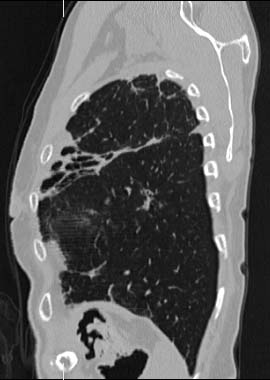

MPR

Data acquired & processed by R. Kato M.D.